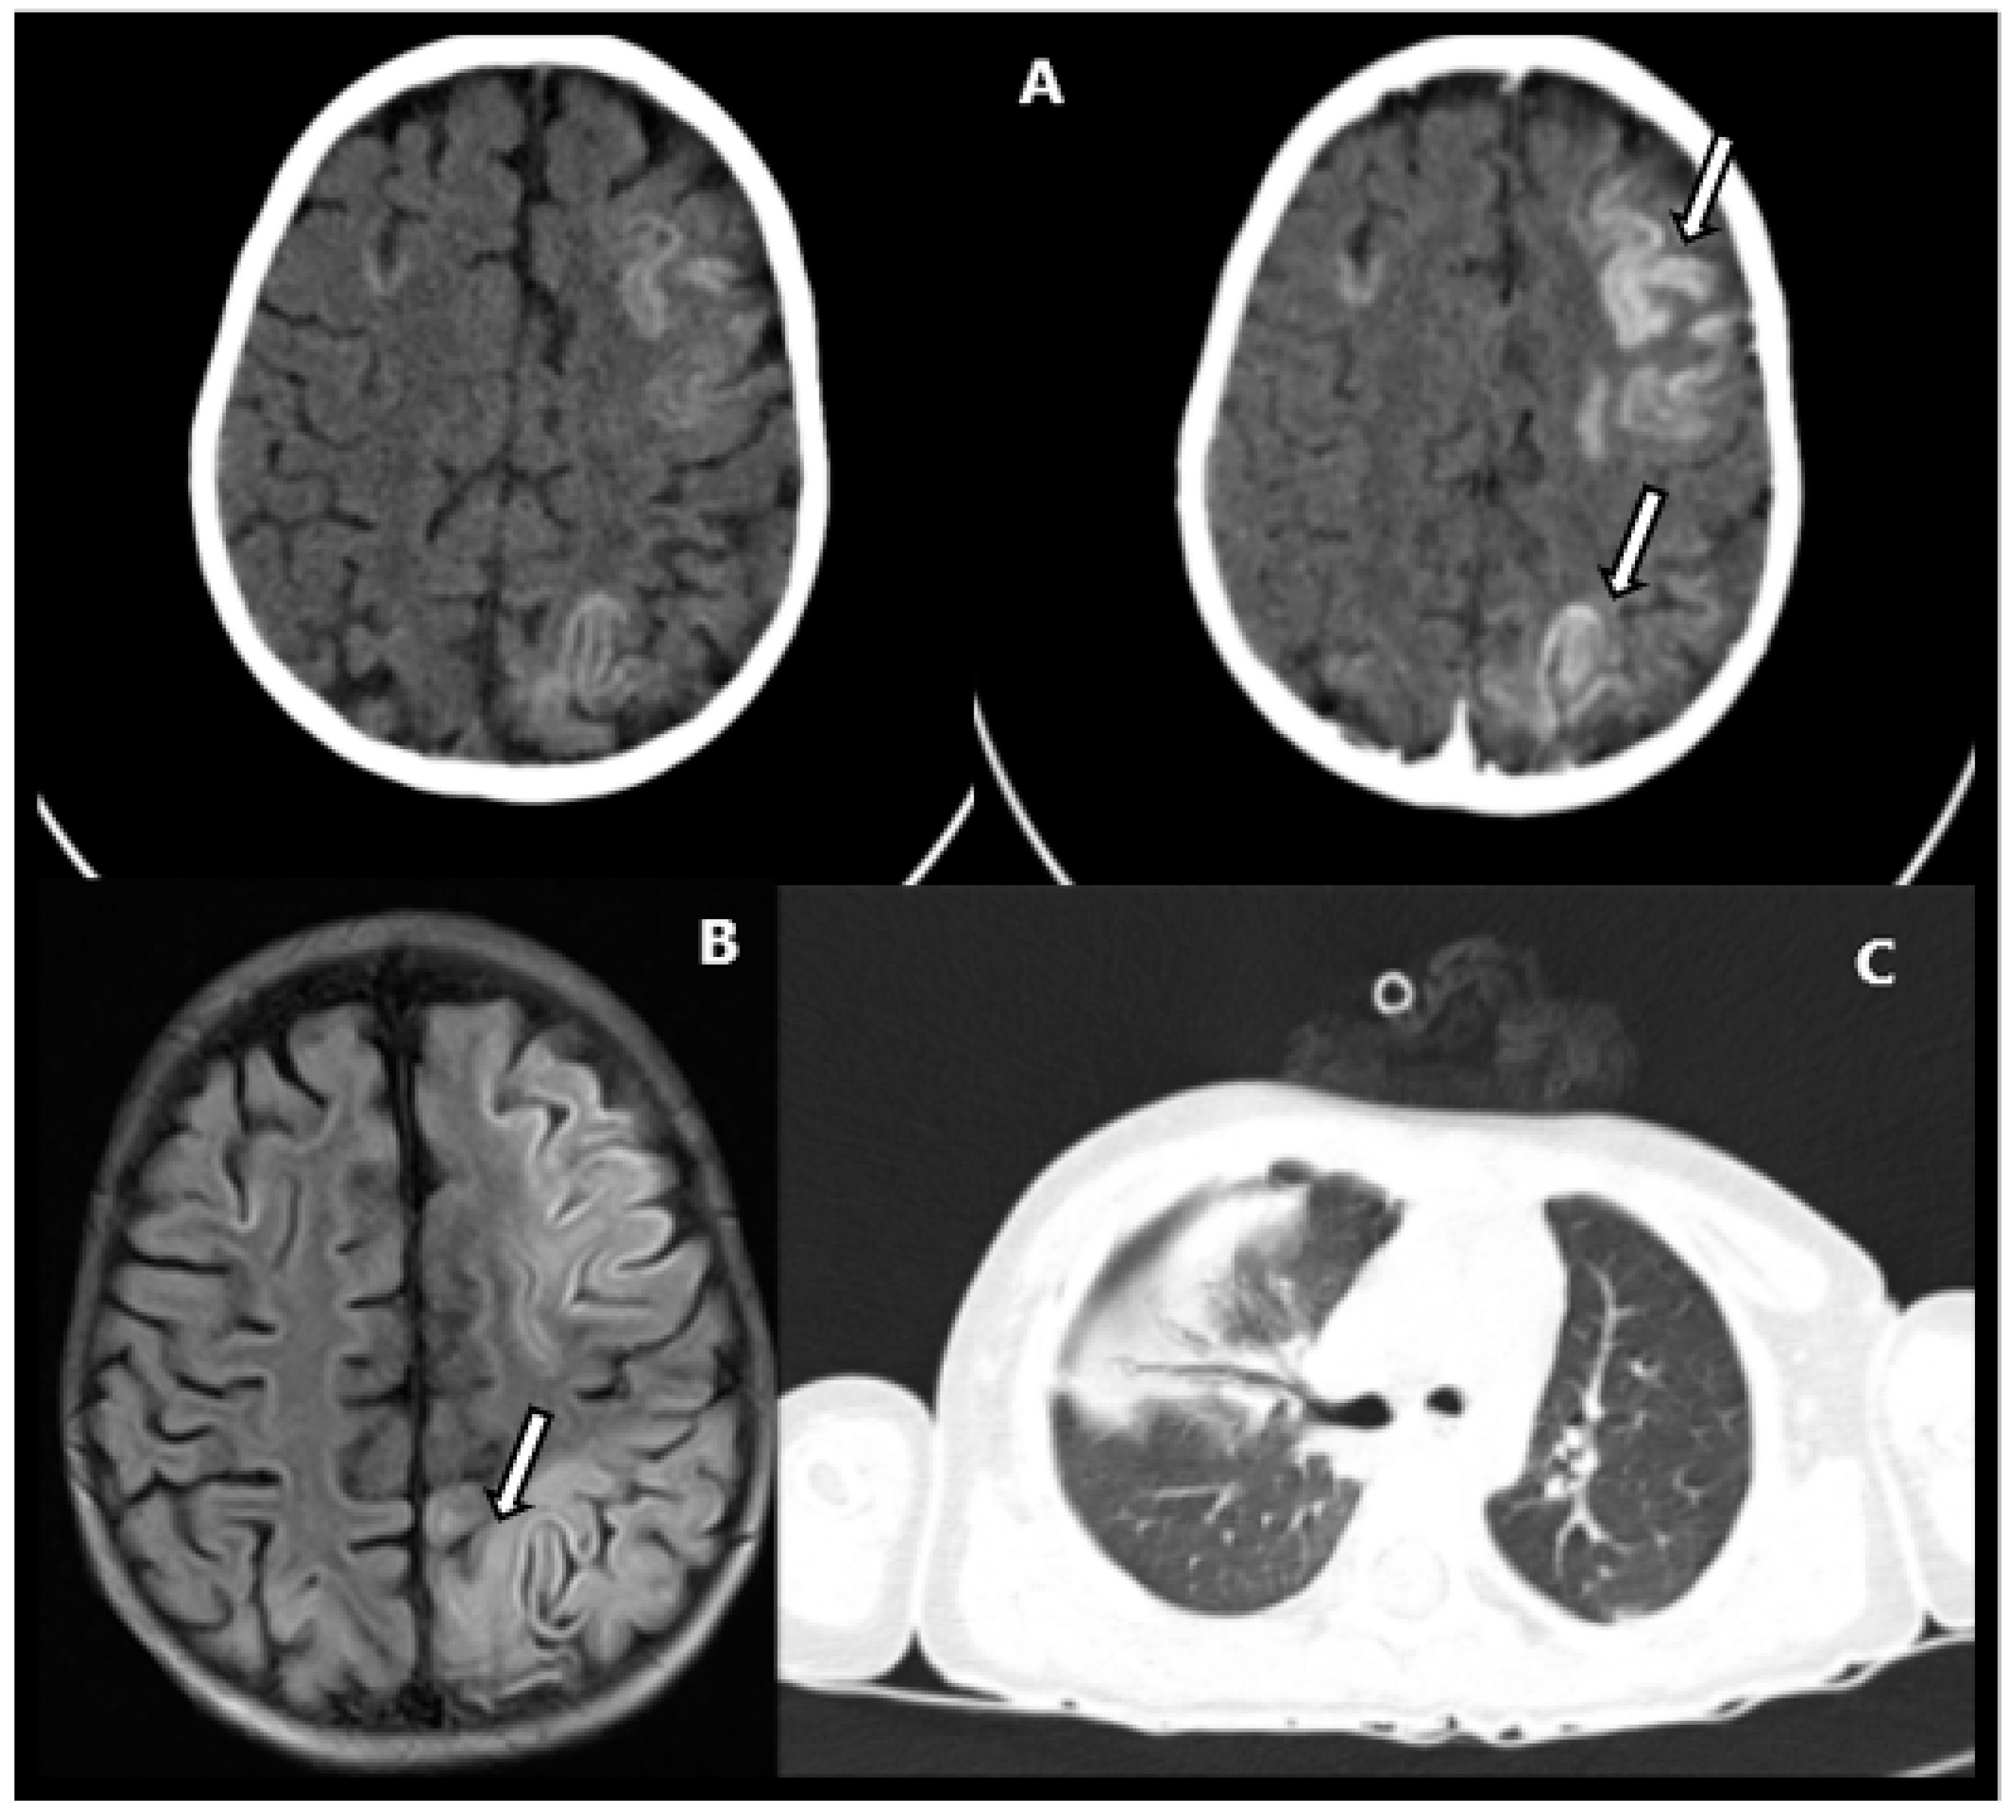

Severe Neurological Manifestation in a Child with Multisystem Inflammatory Syndrome

2. Case Report